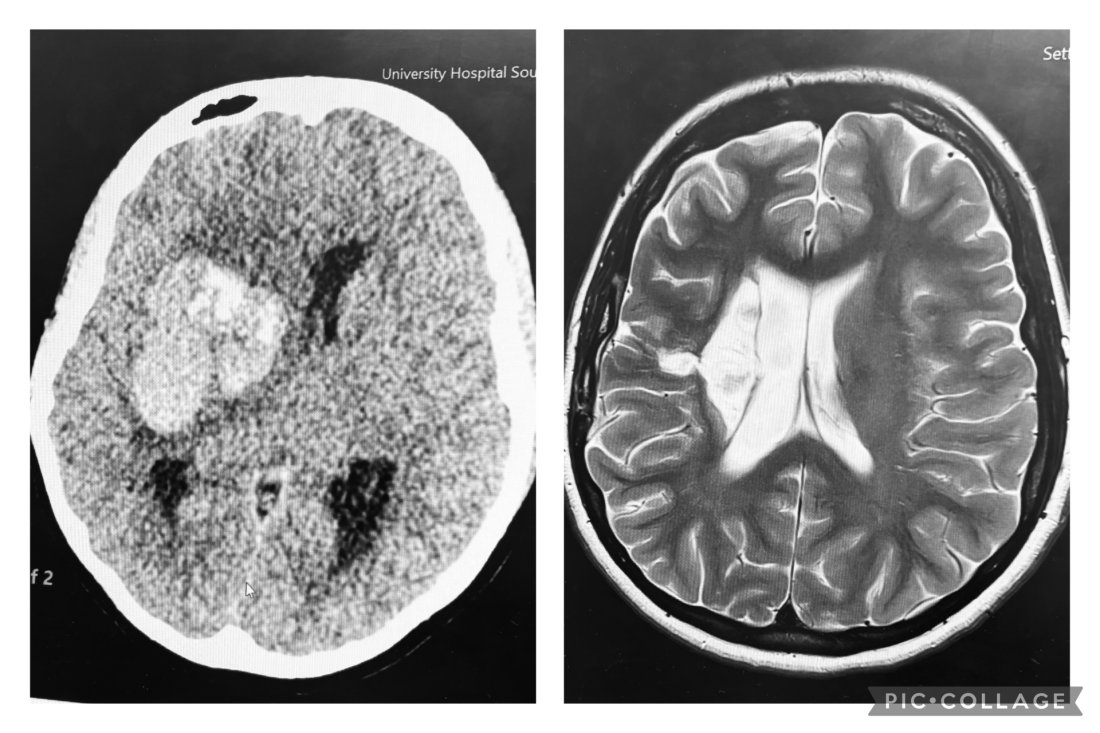

In August 2024, Samuel's wife Ellie suffered an intracerebral haemorrhage and was rushed to the Neuro ICU at the Wessex Neurological Centre, where she was underwent a life saving craniotomy and was placed in a medically induced coma. Ellie woke up 3 days later and spent a further 2 weeks at the centre before continuing her rehabilitation in Salisbury and at Western Community Hospital.